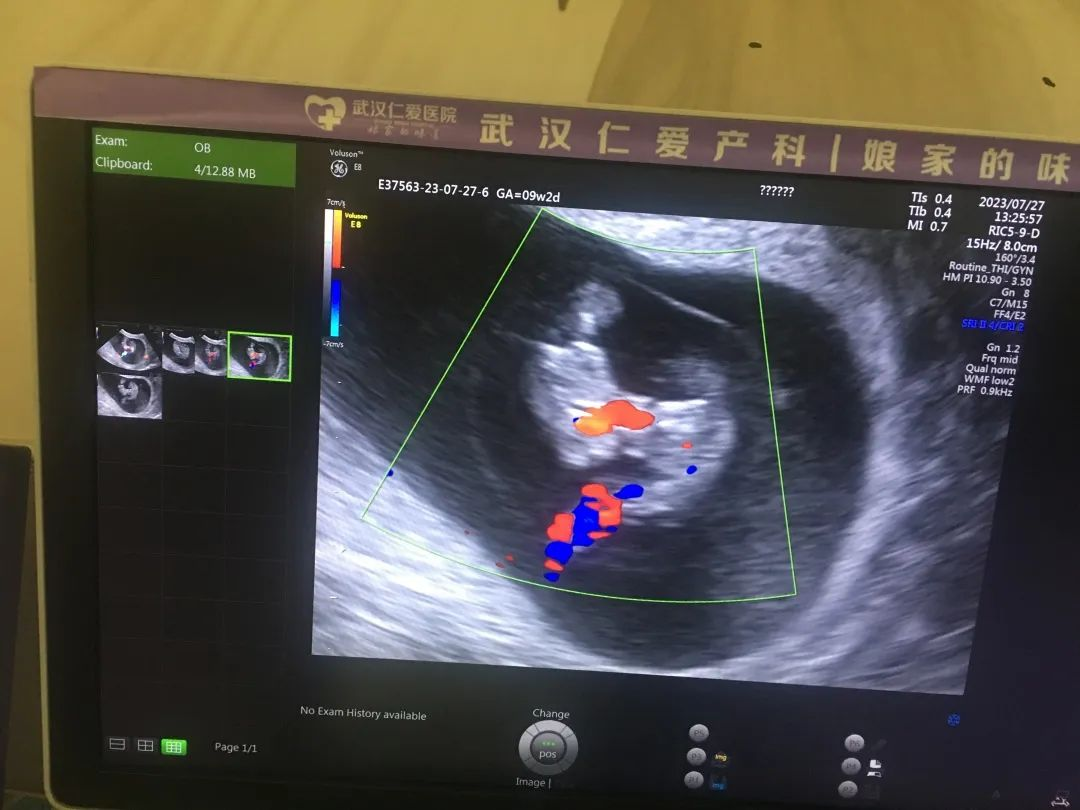

“單絨單羊”雙胞胎發(fā)生率僅為十萬(wàn)分之四,屬極其罕見(jiàn)又極其高危的雙胎妊娠。近日,武漢仁愛(ài)醫(yī)院超聲科就精準(zhǔn)為一位孕8周+的孕媽查出了“單絨毛膜單羊膜囊(MCMA)聯(lián)體雙胎”。